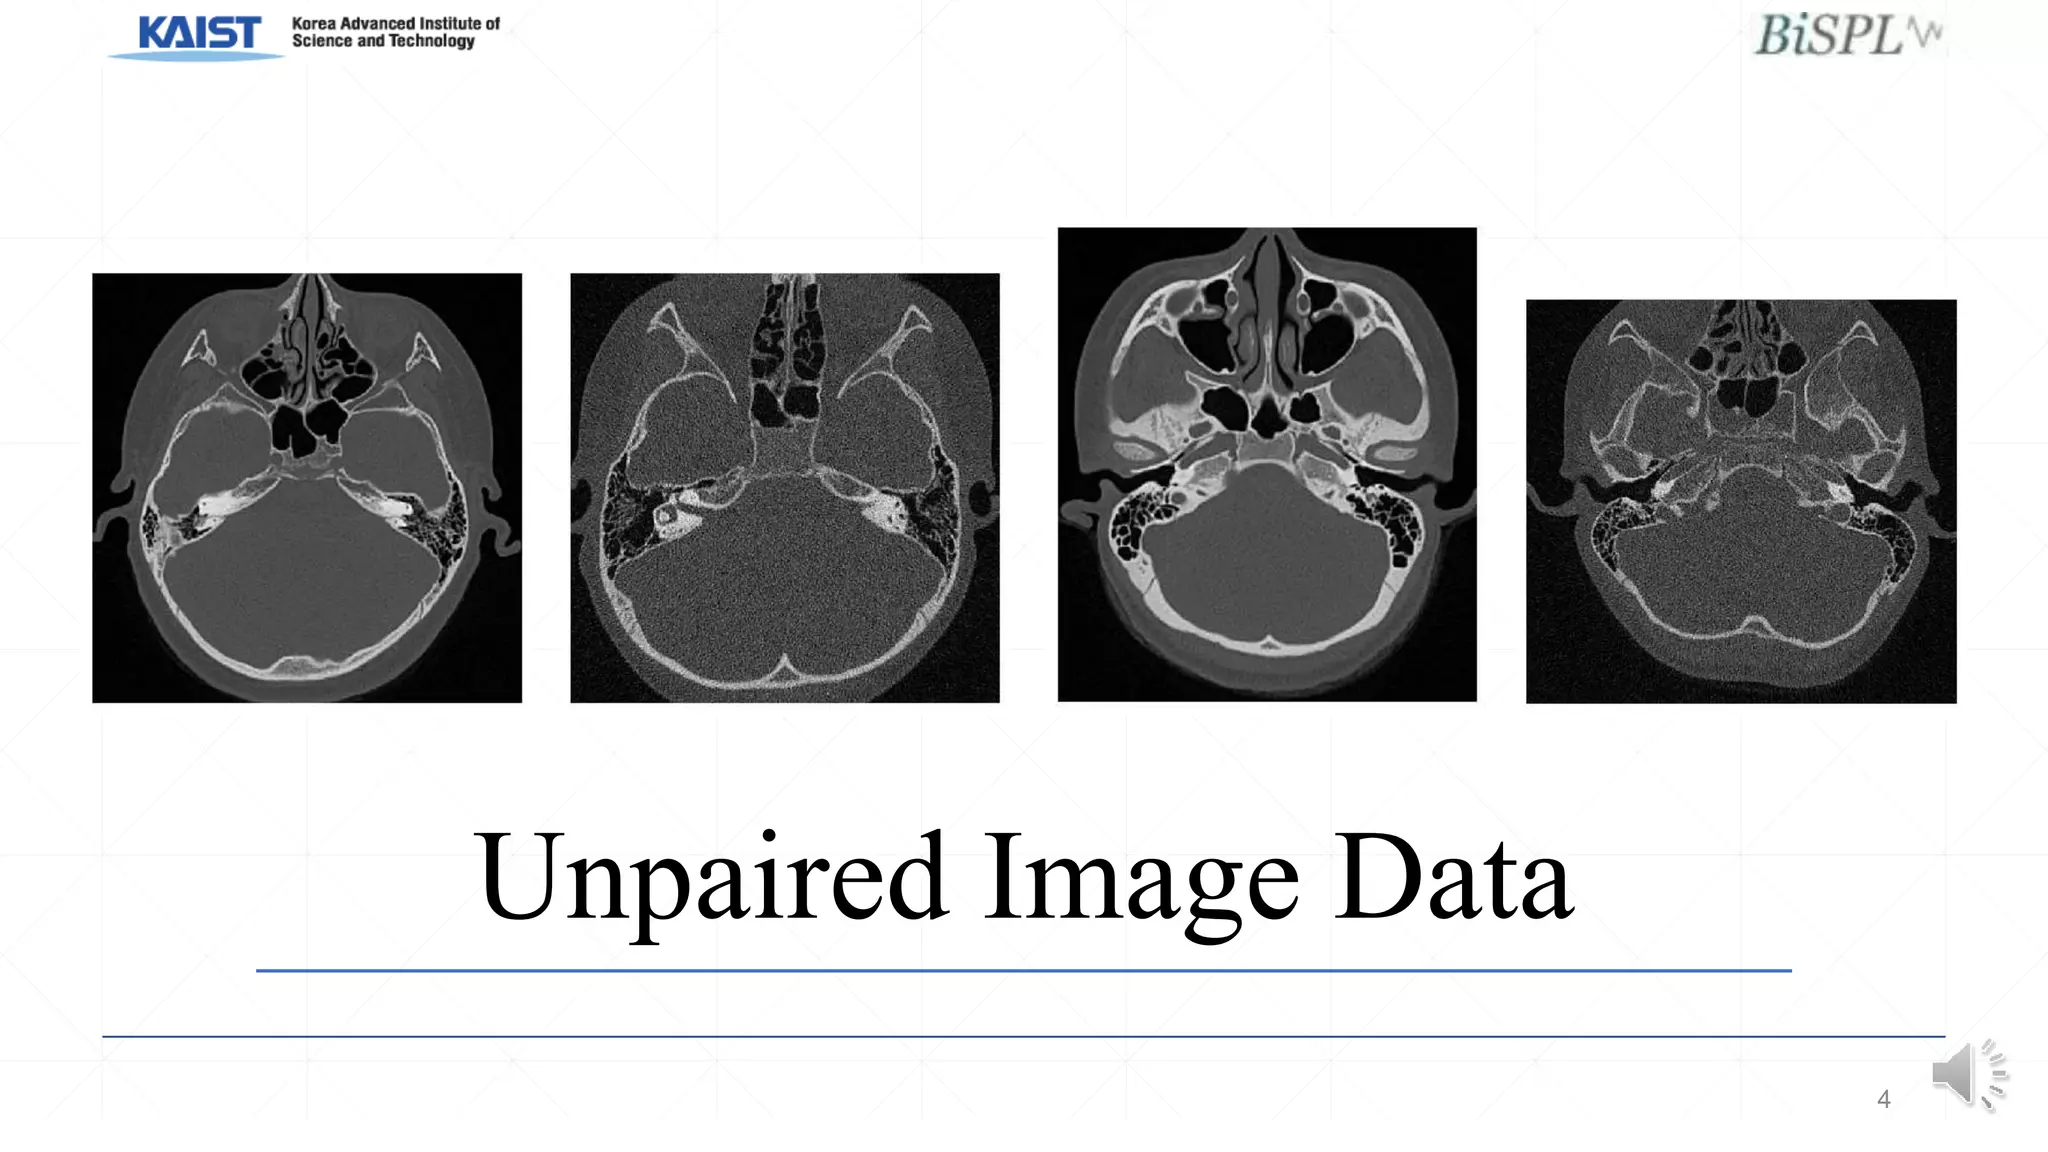

Unpaired Image Data

• #5 However, unlike in most denoising projects, we cannot use supervised learning with paired noisy and clean images as this would expose patients to unnecessary radiation. However, unpaired images of clean and noisy images at different radiation doses are easily available. Therefore, we are faced with the problem of how to learn denoising using unpaired image data.